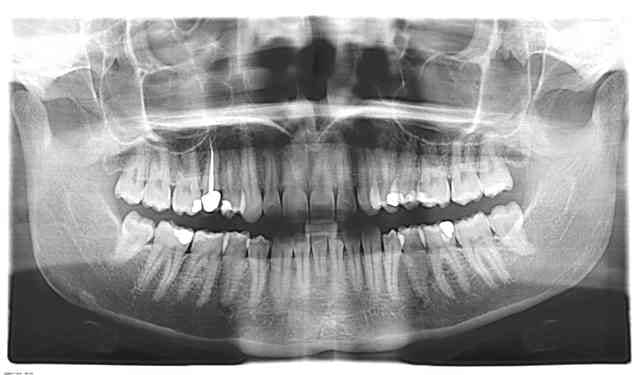

Voila les photos:

1- Préop avec le compo inital infiltré

2-Endo finie

3- 1 semaine apres cavit retiré + compo.

quand on voit la pano, on a l'impression de voir clairement une infiltration sous l'amalgame alors que c'est beaucoup moins évident sous la rétroalvéolaire. Teste, on ne sait jamais.

Il n'est pas improbable que tu aies un 3ème canal sur la 14 mais la radio ne semble pas le mettre en évidence. J'ai le souvenir d'avoir obturer une 24 à 3 canaux et dont le 3ème canal était vraiment trés peu visible voire invisible à la radio car la racine était peu calcifiée.

En regardant bien ta rétro (de tres bonne qualité), on voit quand meme aux 2/5 apicaux une petite ligne blanche horizontale faisant quand meme penser hélas à une fracture.

Concernant la suspicion de carie sur 16 d'apres la pano, c'est simplement un artefact du au filtre de renforcement des contours qui donne un burnout sous l'amalgame. La rétro montre bien qu'il n'y a pas de probleme.

A Athos: le trait que tu veux me montrer n'est je crois qu'une simple trabéculation osseuse (le trait est radioopaque, alors une fracture est radioclaire et de toutes les facons une felure est invisible à la radio)

Quand bien même felure il y aurait a cet endroit, on devrait voir au moins un épaississement ligamentaire.